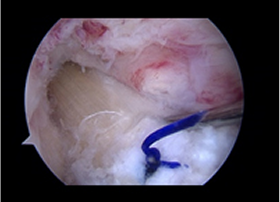

봉합이미지

1 ) 봉합술

일반적으로 관절경을 이용하여 반월연골판을 봉합합니다. 봉합하는 방법에는 여러 가지가 있습니다.

첫 번째 방법은, 관절경 시야에서 파열된 부위를 확인한 후 봉합 기구를 이용하여 관절 내부에서 시작해

관절 외부로 실을 뽑아내어 관절막에 매듭을 만드는 방식입니다. 두 번째 방법은, 관절 외부에서 유도관을 이용하여

파열 부위 및 반월연골판을 통과시킨 후 봉합사를 관절 외부로 빼내어 관절막에 매듭을 만드는 방식입니다.

바른마디병원 반월연골판 봉합술은 파열의 위치와 크기에 따라 적절한 방법을 선택합니다